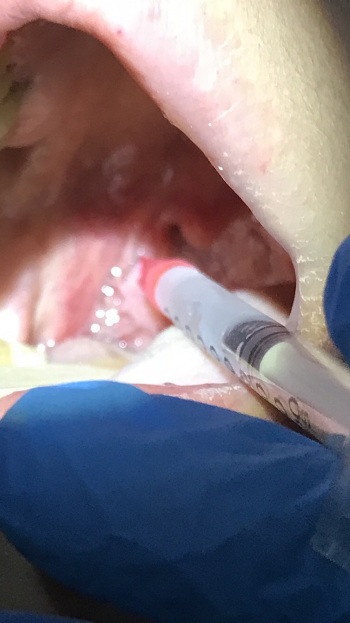

При осмотре: на передней нёбной дужке справа визуализируется округлое образование на ножке, размером 1,5*1,0 см, не спаянное с окружающими тканями, безболезненное при пальпации.

Фото 1: Доброкачественное образование нёбной дужки справа

Фото 2: Местная инфильтрационная анестезия

Фото 3: Удалённое образование СО2 лазером

Фото 4: Нёбная дужка после удаления